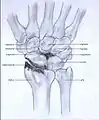

Post-traumatic osteoarthritis can be classified into four stages.[1][6] These stages are similar between SLAC and SNAC wrists. Each stage has a different treatment.

- Stage IV: the osteoarthritis is located in the entire radiocarpal joint and in the intercarpal joints. It also may involve the distal radio-ulnar joint (DRUJ).

Stage IV